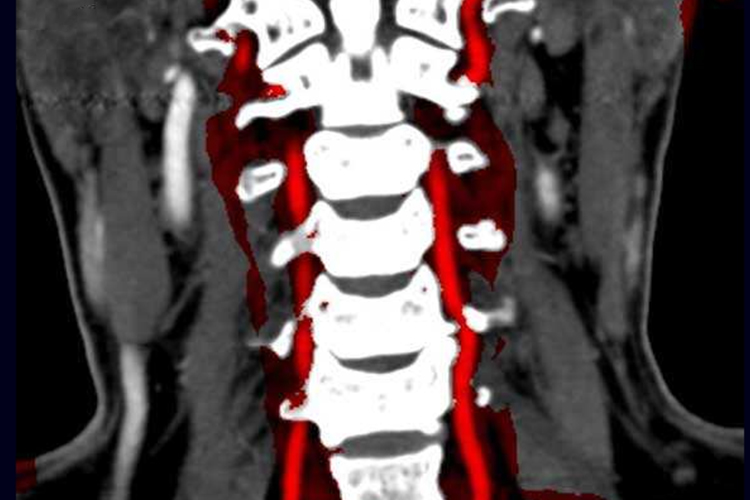

椎动脉型颈椎病:当颈椎关节增生时,可对椎动脉造成挤压和刺激,引起脑供血不足,产生头晕、头痛等症状。检查可显示椎节不稳及钩椎关节侧方增生。